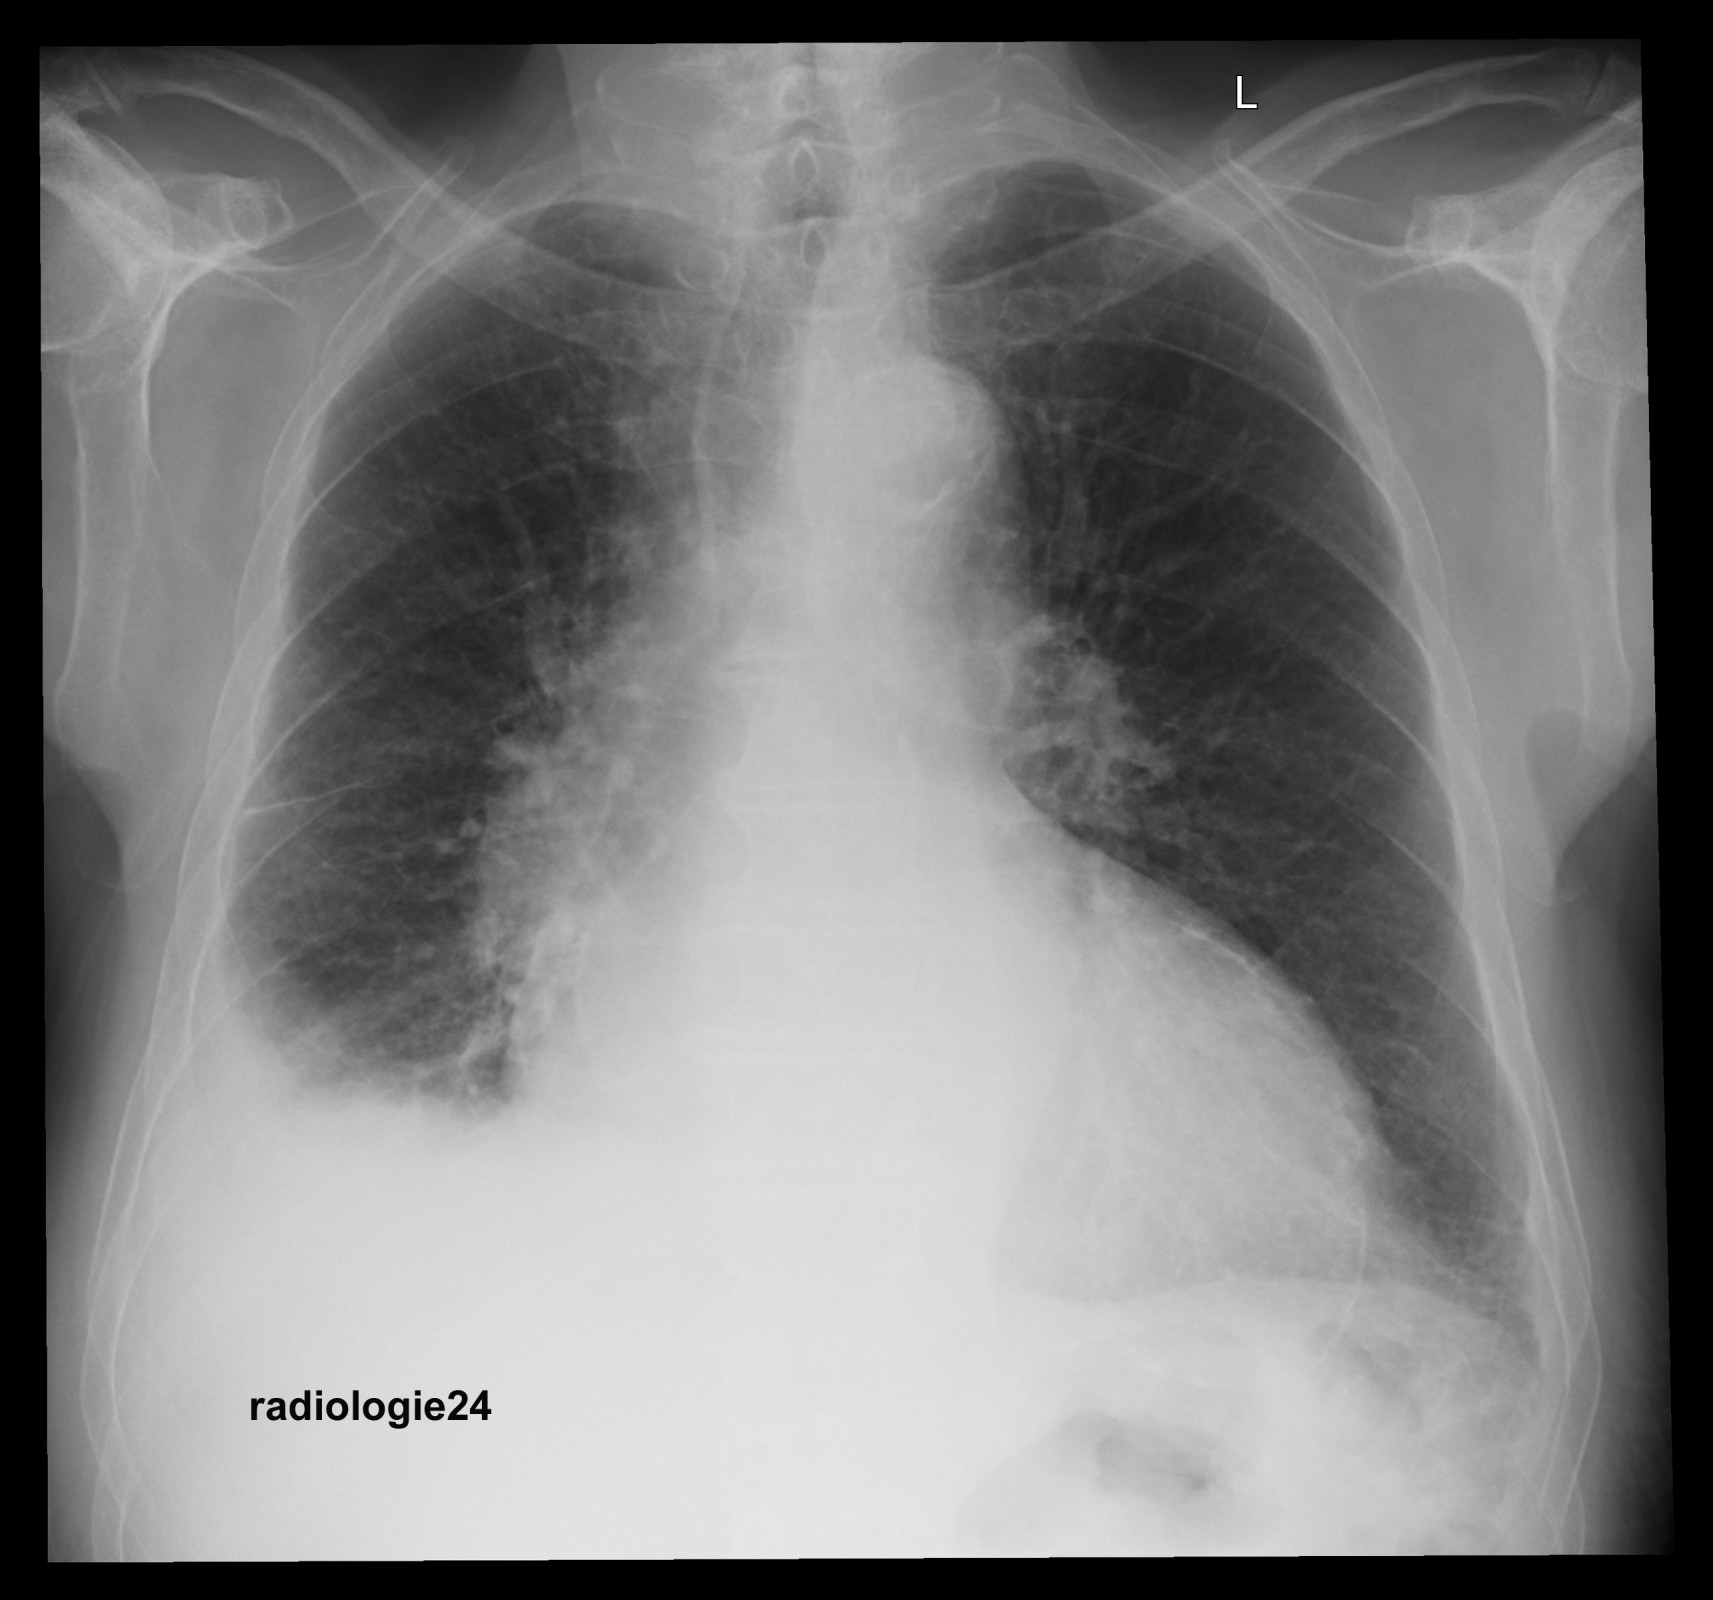

Röntgenfall des Monats Februar 2018 mit Auflösung

75 jähriger Patient Zunehmende Belastungsdyspnoe. Ihre Diagnose? Nebenbefunde?

Bild vergrössern

Link zur Auflösung mit ausführlichem Befund:

https://www.radiologie24.ch/radiologie-mediathek/roentgenfall_des_monats